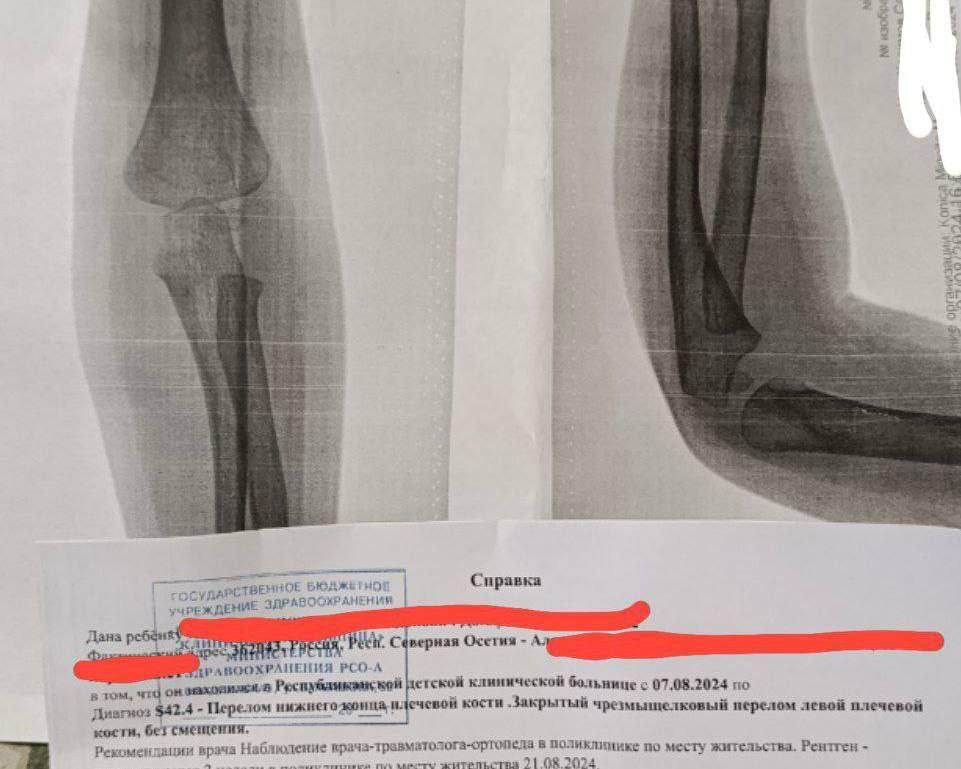

Во Владикавказе воспитательница детского сада сломала руку двухлетнему ребёнку.

Мать малыша вызвали в садик, где сообщили, что с рукой ребёнка «что-то не так». В травмпункте врачи обнаружили перелом плечевой кости. Родители потребовали показать видеозапись с камер наблюдения, на которой видно, как воспитательница грубо тянет ребёнка за руку и бросает его на пол.